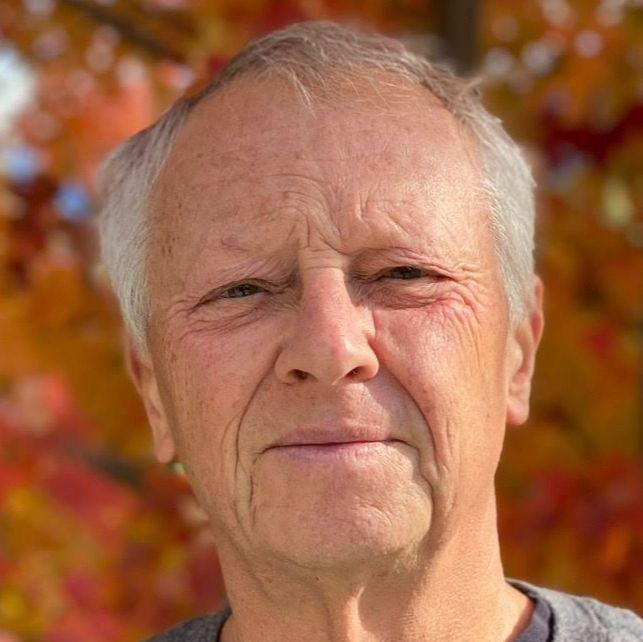

Time flies. Looking back, David Townsend, PhD, can hardly believe it has been twenty-five years since he and his team, based at the University of Pittsburgh, developed the device in collaboration with Ronald Nutt, PhD, CEO of CTI PET Systems, in Knoxville, Tennessee, USA. Since then, numerous innovations have propelled PET/CT to even higher and wider applications.

The story of PET/CT begins in the early 1970s in Geneva, Switzerland, almost 30 years before the first PET/CT scanner was developed. Back then, Townsend joined the European Organization for Nuclear Research (CERN), the European particle physics laboratory. At the time, PET was far from being a clinical tool—it was a research project with uncertain applications. Townsend started looking at potential detector applications for PET in 1975 along with Alan Jeavons, PhD.

Four years later, Townsend moved to University of Geneva Hospital to focus entirely on PET scanner development. In 1988, while working at University of Geneva Hospital, Townsend collaborated with CTI PET Systems and Terry Jones, DSc, from Hammersmith Hospital, London, UK, to design and build a cost-effective, rotating PET scanner based on the BGO (bismuth germanium oxide) block detectors developed by CTI PET Systems. Townsend and Jones‘s rotating prototype scanner imaged patients at the University of Geneva Hospital and was later commercialized by CTI PET Systems as the Advanced Rotating Scanner (ART) that represented a cost-effective PET scanner.

At the 1998 Society of Nuclear Medicine (SNM) annual meeting in Toronto, Canada, Townsend shared the first clinical PET/CT images with the world. Townsend looks back, “It was a very exciting time to be to be involved in nuclear medicine.” CTI and Siemens did not begin looking at the commercialization of PET/CT until about 1999, after enough clinical image data was acquired to convince physicians that it was a useful clinical concept.

The co-inventors, Townsend and Nutt, and members of the team remained involved in PET/CT’s development. In November 2000, the new scanner was unveiled to the world at the Radiological Society of North America’s (RSNA) annual meeting in Chicago, Illinois, USA. In December of the same year, the PET/ CT concept and prototype design was honored by TIME magazine as “Medical Invention of the Year.”1 By mid-2001, the first commercially available Siemens Biograph PET/CT system was installed at the University of Pittsburgh.

“’How about adding CT to PET?’…For us, as scientists and engineers, it made sense. You’re combining complementary information—the high-resolution anatomical detail of CT with the functional imaging of PET—and offering physicians both in a single device.”

Reflecting on the progress over

the past 25 years, Townsend says

“Nowadays, you have very powerful

instruments compared to what we

had in 2000. And they provide superb,

unbelievable imaging capabilities in

times we didn’t even dream of back in

those days. The development of total body

imaging with large field-of-view

systems is now a reality. We used to

work with 15-cm axial extent, and now

you have a system like Biograph Vision

Quadra, which has 106-cm axial field

of view (aFOV). You can look at

dynamics between different organs,

which we could never do, and that’s

been a tremendous step forward.

Because you know we would image

either the brain or the heart or the liver,

maybe the lungs, lower abdomen—

but the body is a total system.”

Full circle: from pioneer to patient

Last year, Townsend himself

underwent a PET/CT scan following

the discovery of a suspicious nodule

in his left lung. The PET/CT was

consistent with an adenocarcinoma

that was confirmed by biopsy.

Fortunately, it was an early stage 1

tumor that was removed surgically

and a 6-month follow-up scan showed

no evidence of disease. Reflecting on

his own patient experience, Townsend

recalled that the imaging team who

performed the scan at the University

of British Columbia Cancer Centre,

Vancouver, Canada, were aware of

Townsend‘s background. The

technologist who gave him the

injection of FDG quipped, “‘I guess I

don’t need to explain the imaging

procedure to you, do I?‘” remembers

Townsend, with a smile.

And what are his personal hopes for the next 25 years of PET/CT? Conti pauses, then offers two wishes: “More tracers that unlock the full potential of our amazing technology. And that PET/CT becomes more accessible to patients earlier in the care pathway. Right now, a patient needs to have a cancer diagnosis to maybe get a PET/CT scan. I would love a world where PET/CT is routine, where patients receive a PET/CT when there is suspicion of cancer.” As for Townsend? His wish echoes a similar sentiment: that PET/CT technology is widely available to all patients no matter where they live.